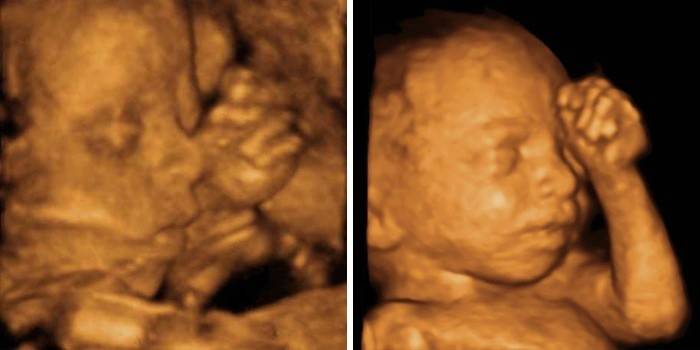

Vývoj plodu v dvadsiatom štvrtom týždni: veľkosť a pohlavie

Po 24 týždňoch tehotenstva dieťa dorastie na 30 cm a pribúda na hmotnosti asi 600 g. V maternici je už stiesnená, hoci sa môže stále pohybovať celkom aktívne a meniť svoju pozíciu niekoľkokrát za deň, aj keď nebude môcť robiť kormidlo. Plod je aktívny a jeho pohyby sú silnejšie a sebavedomejšie. Počas bdelosti sa dieťa cíti aktívnymi pohybmi, jeho pohyby jasne pociťuje jeho matka aj iní - ak si položíte ruky na brucho alebo ho sledujete. Dieťa môže škytavku alebo kašeľ, je to ako rytmické kontrakcie v žalúdku. Dieťa si vyvinulo rytmy spánku a bdelosti, väčšinu času, keď spí a sníva, a počas bdelosti aktívne sa mieša.

Mozog sa aktívne zdokonaľuje - vytvára gyrusy, drážky a kortikálne centrá s nervovými spojeniami. To umožňuje vylepšiť reflexy a zmyslové orgány. Dieťa teraz môže vidieť a počuť, rozlíšiť vkus a dotyk. Už ukazuje prvé emócie a je potrebná komunikácia s dieťaťom, mamou aj otcom. Dieťa získalo svoje charakteristické rysy tváre a teraz už bude vyzerať takmer ako pri narodení, v lícach sa bude nahromadiť iba malé množstvo tuku. Nemenej aktívne bude hromadiť hnedý tuk v telových dutinách a pod kožou, tento tuk dodáva vysokú úroveň tepelnej energie a pomáha v prvých dňoch života dieťaťa udržiavať jeho energetický metabolizmus a telesnú teplotu. Vďaka hormónu vlastného rastu dieťa aktívne rastie a priberá na váhe.